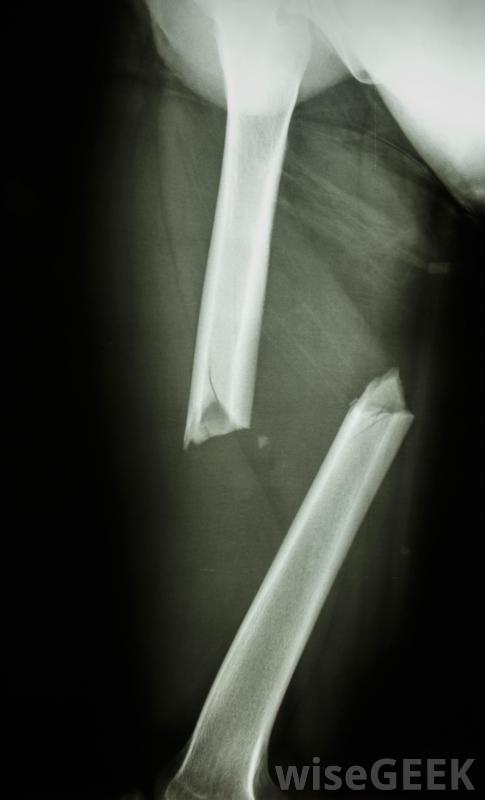

将病人带到手术室进行全身麻醉进行内固定,内固定可使用多种器械,包括螺钉、钉子、杆、板,别针,外科医生将利用像X光片这样的医学影像学研究来了解骨折的性质,并制定一个有效和适当的治疗方案。这包括准备好内固定装置,以便为手术做好准备。病人被带进手术室,接受全身麻醉这样外科医生就可以进入手术部位,安装设备,然后闭合伤口。

内固定有助于骨折正常愈合这通常是外科手术中被称为开放复位内固定(ORIF)的一部分。"开放复位"是指打开病人的身体,让他们清楚地看到骨折,然后把骨头放回原位,而不是闭合复位,骨科医生保持皮肤完好无损,通过操纵该区域的骨骼将骨折固定到位。骨折的外科矫正更具侵略性,但也可以更精确。

骨折有时需要外科手术来重新排列骨骼并将其固定到位